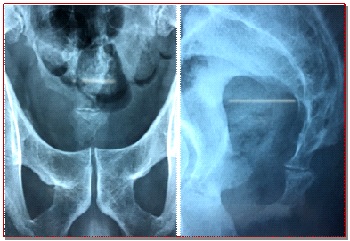

The aim of this study was to evaluate the clinical outcome of coccygectomy those who were refractory to conservative treatment. Twenty patients (5 males, 15 females) underwent total coccygectomy when coccygodynia did not responding to medical treatment July 2013 to September 2018. All the patients timely attended with non-traumatic (n = 12) and traumatic (n = 8) cause with mean follow-up visits of 24 months (range 18-28 months). The outcome pain intensity was evaluated by visual analogue scale (VAS) in sitting position and during daily activities. Three patients had infection which improved after antibiotic therapy. The VAS improved from 6.4 ± 0.9 to 2.1 ± 0.9 for sitting and from 5.8 ± 0.9 to 1.6 ± 0.6 for daily activities. Improvement in pain and daily activities were significant at the final follow-up. Ninety percent patients were satisfied with the operation.